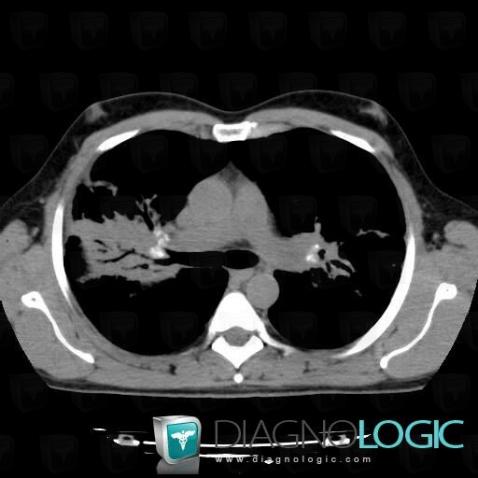

Sarcoïdose, Parenchyme pulmonaire, Scanner

Voici les informations spécifiques à l'image clé ci dessus:

- Diagnostic Sarcoïdose, Localisation(s) Parenchyme pulmonaire, comportant les gammes Epaississement péri broncho vasculaire / Epaississement septal irrégulier